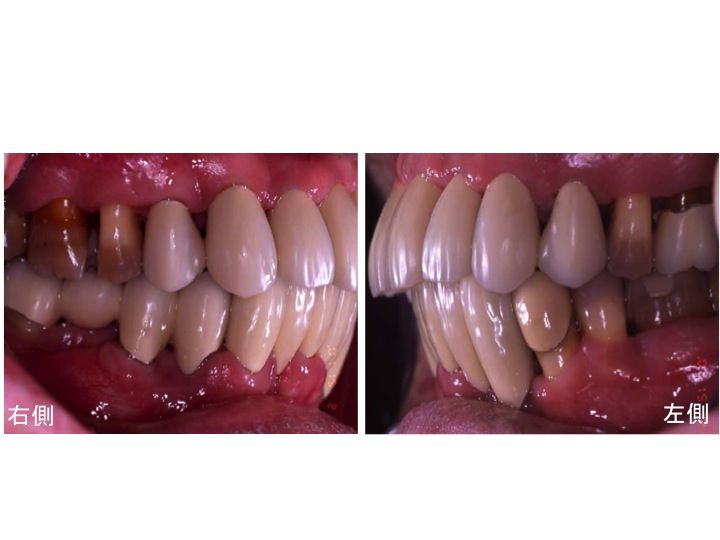

本日は侵襲性歯周炎(ししゅうせい ししゅうえん)のケースレポートです。

患者様は初心時40歳でした。

歯がグラグラで

歯周ポケットは10mm以上あるところも多く、

ほとんどの部位で 歯肉の腫れ、出血が認められました。

このような場合、

通常多くの歯で抜歯となります。

治療を行なわなければ50歳になるころには

ほとんどの歯はなくなっているでしょう。

40歳で重度の歯周炎ですから

20歳代ですでに歯周病がかなり進行していたことが考えられます。

早急に徹底した歯周病治療を行なわないといけない状態です。